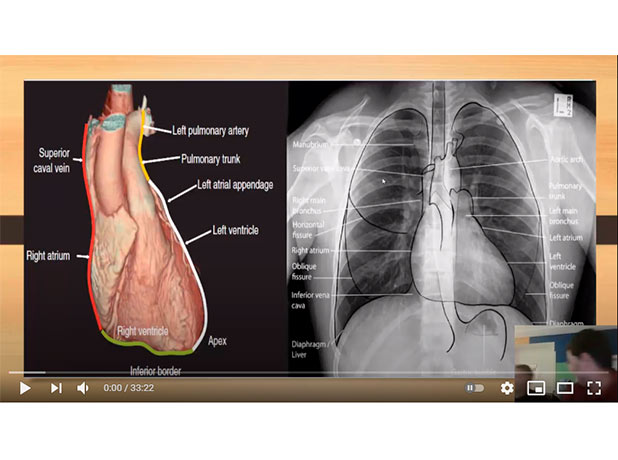

Cardiac anatomy and rapid introduction to Tetralogy of Fallout

Mohamed Gibreel , FEBR (Fellowship of Egyptian Board of Radiology ) Cardiac imaging consultant at Aswan heart center -Magdi Yacoub Foundation , Egypt